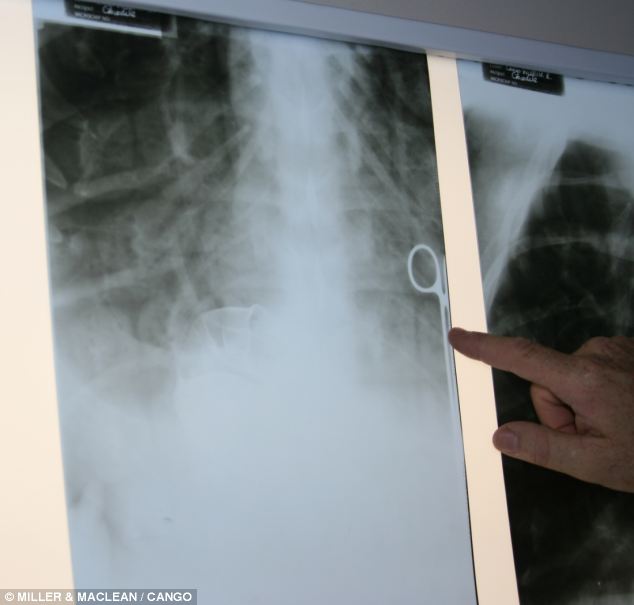

After arriving at the vet, an x-ray revealed that the can was stuck in the left side of Liz's gut.

To attempt to remove the can without any intrusive procedure, we inserted a hosepipe into her tummy and filled it up. It was then a case of counting 'one, two, three' and flipping the body 45 degrees in the air to force the water out. It was exhausting and we tried it five times, but it didn't work. The then 25-year-old Liz, had crunched the can into such a jagged shape that even clamps were unable to dislodge it from a fold of flesh.